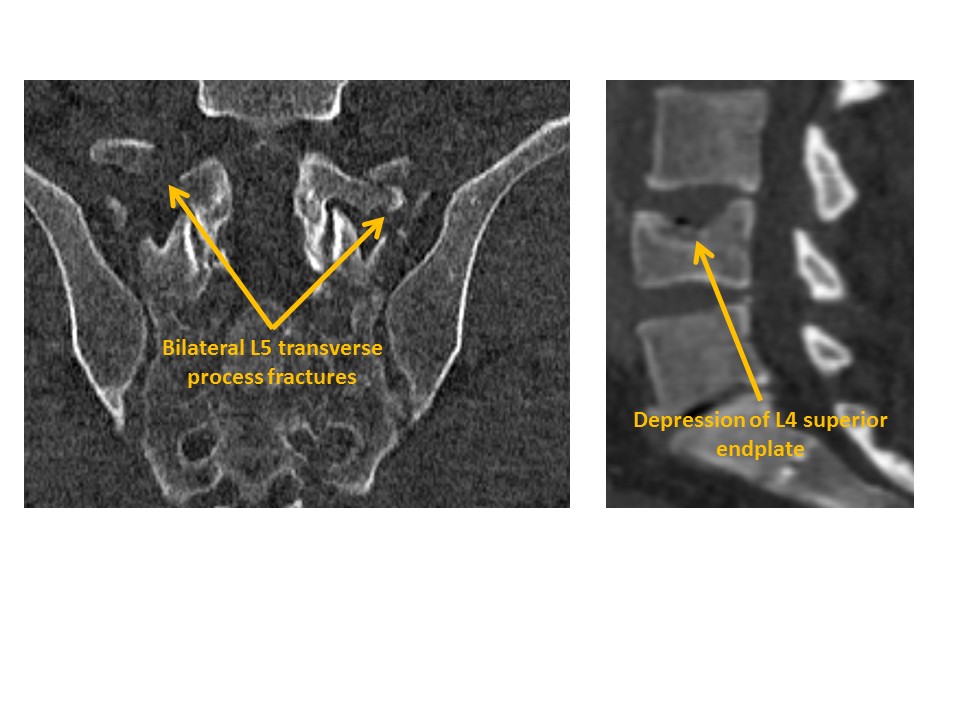

There are compression fractures, transverse process fractures, or malalignment. |

No | NA |